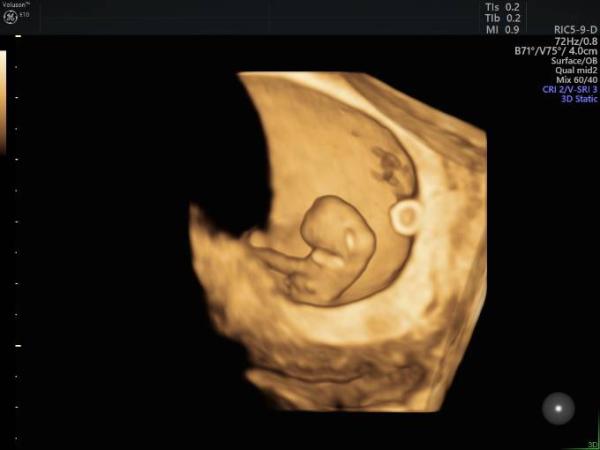

Heute hatte ich nun auch wieder FA Termin mit Mutterpassübergabe. Käfer ist 1,7cm groß, bin ca. 8+2. Herzchen hat brav gepochert! Und hier wieder ein Bild in 3D

Bild zu wieder ein kleines 3D Bildchen:) - Forum für Januar - Mamis